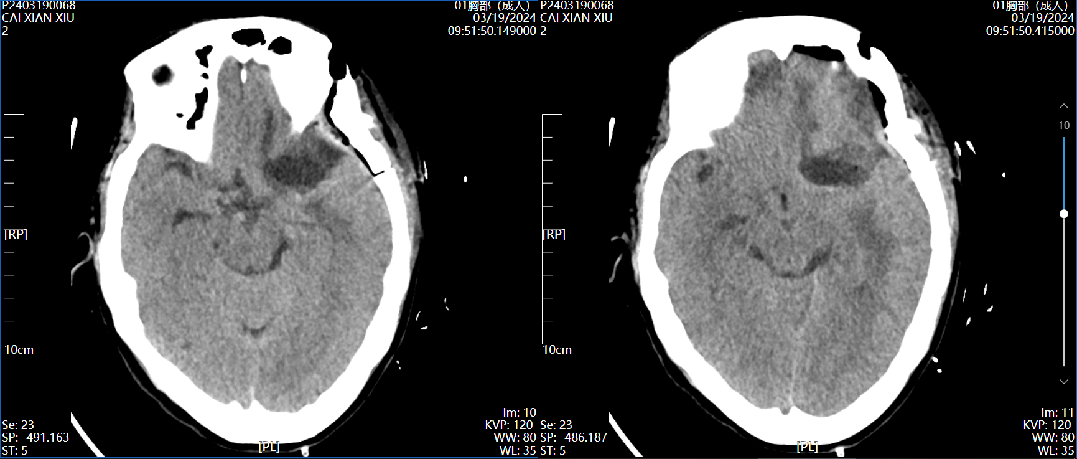

术后第一天CT    2024.03.19